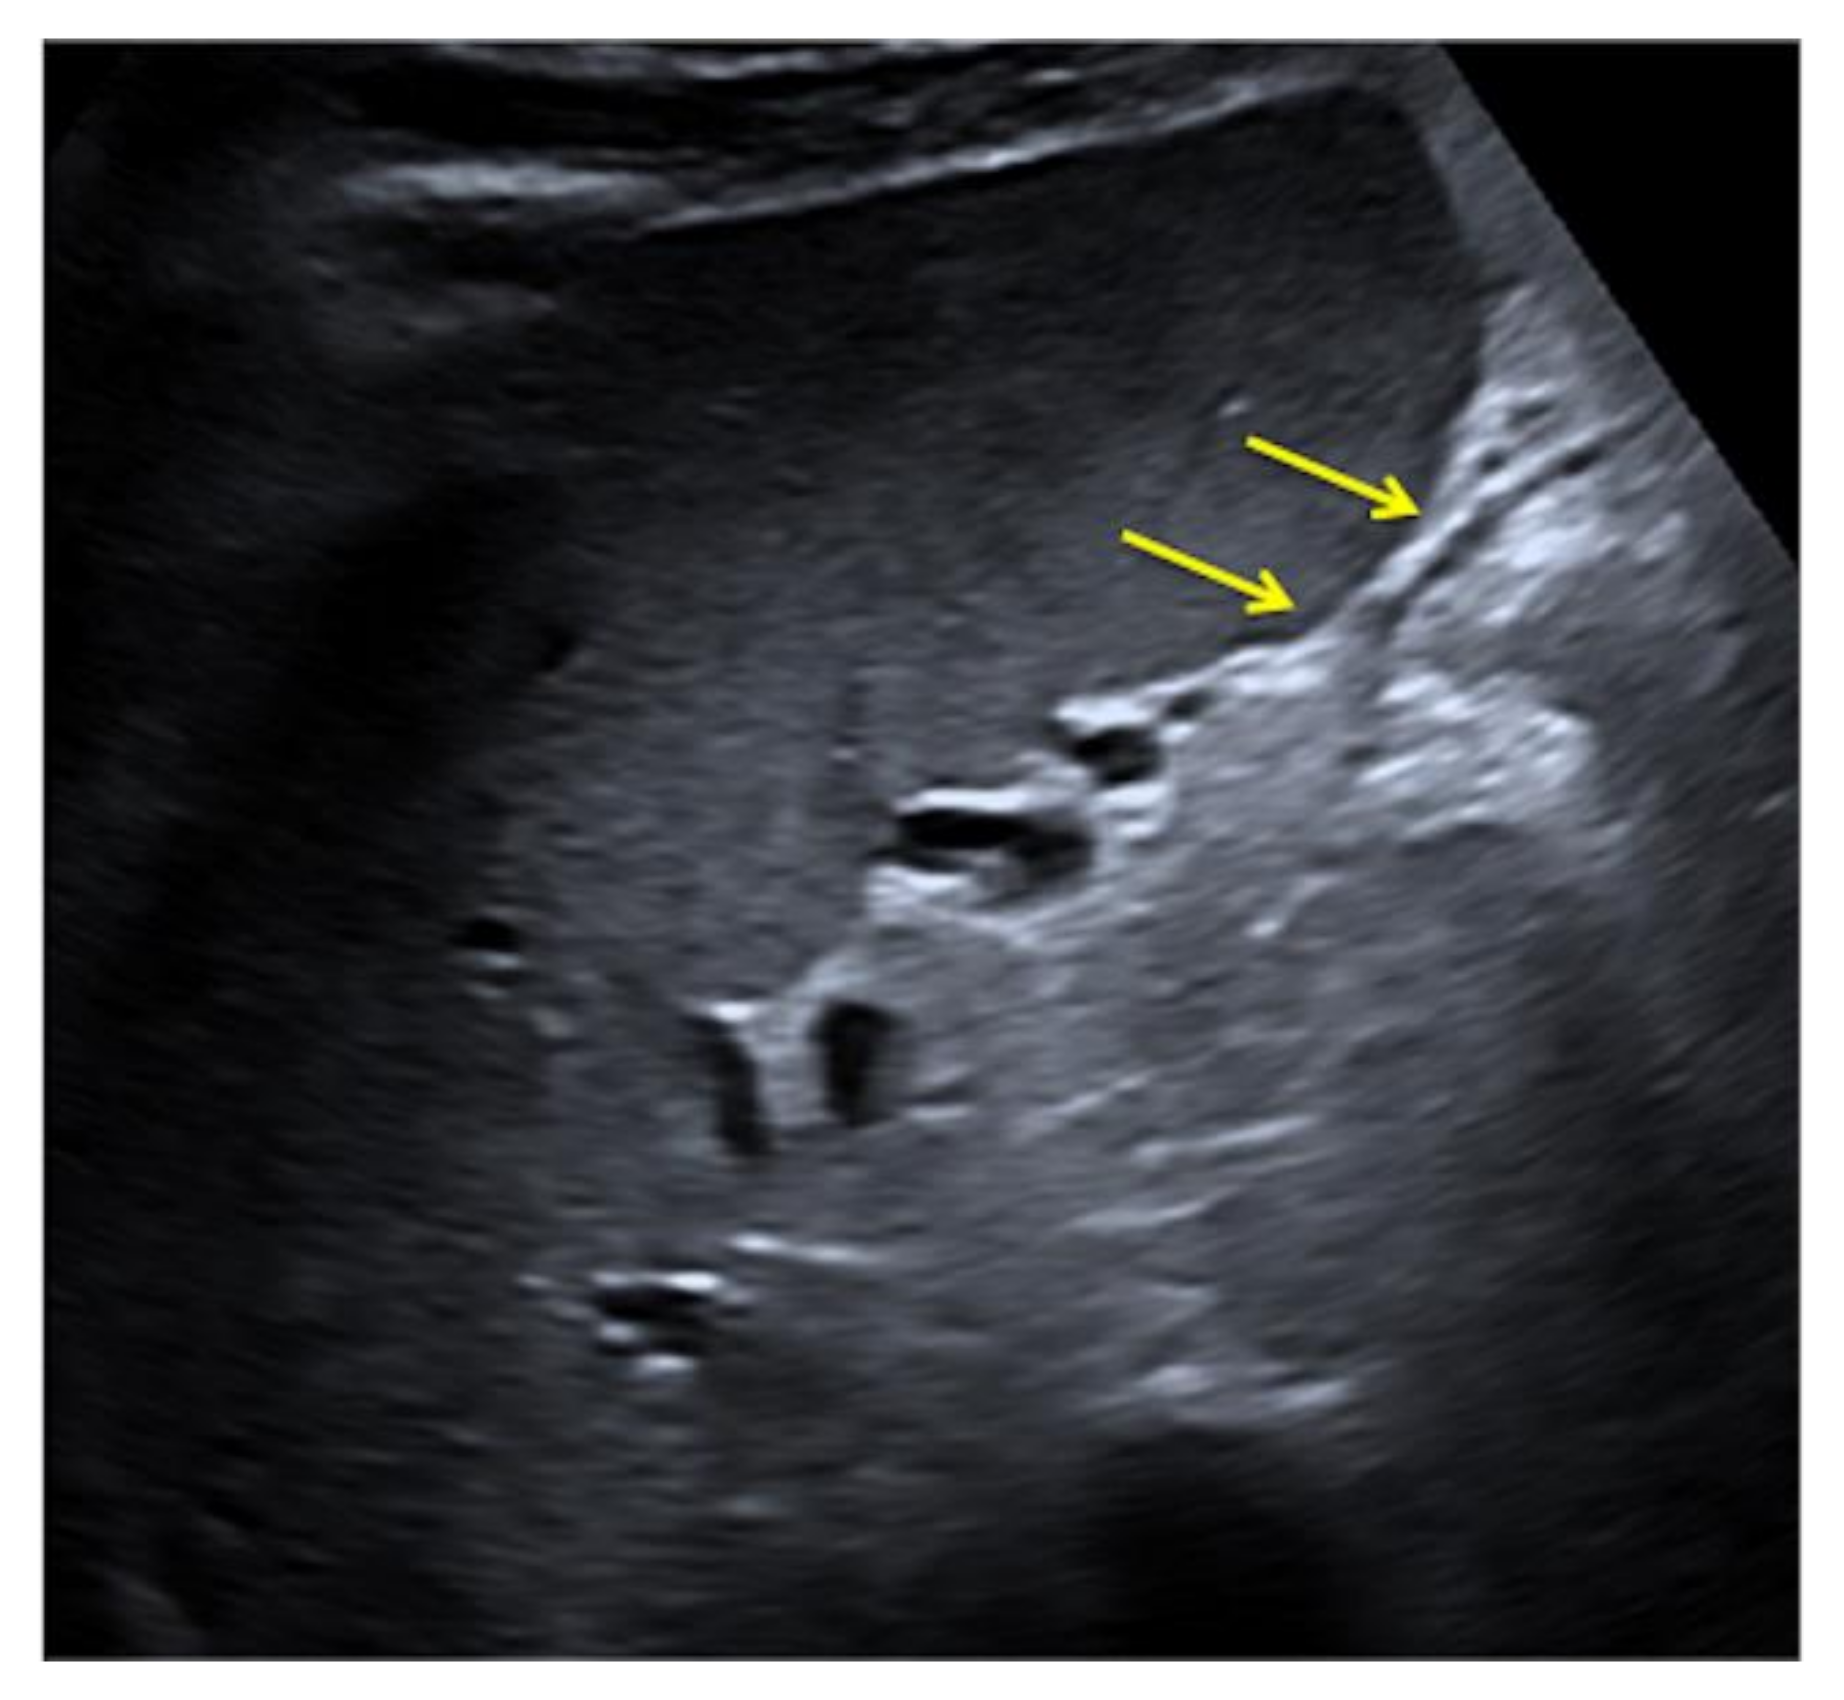

3.1. Bad Artifacts

3.1.1. The Side Lobe Artifact

3.1.2. The Mirror-Imaging Effect

3.1.3. The Speed-Displacement Artifact (Propagation Velocity Artifact)

3.1.4. Refraction Artifacts

3.1.5. Reverberation Artifacts

3.1.6. Image-Adaptation Artifacts

3.1.7. Anisotropy